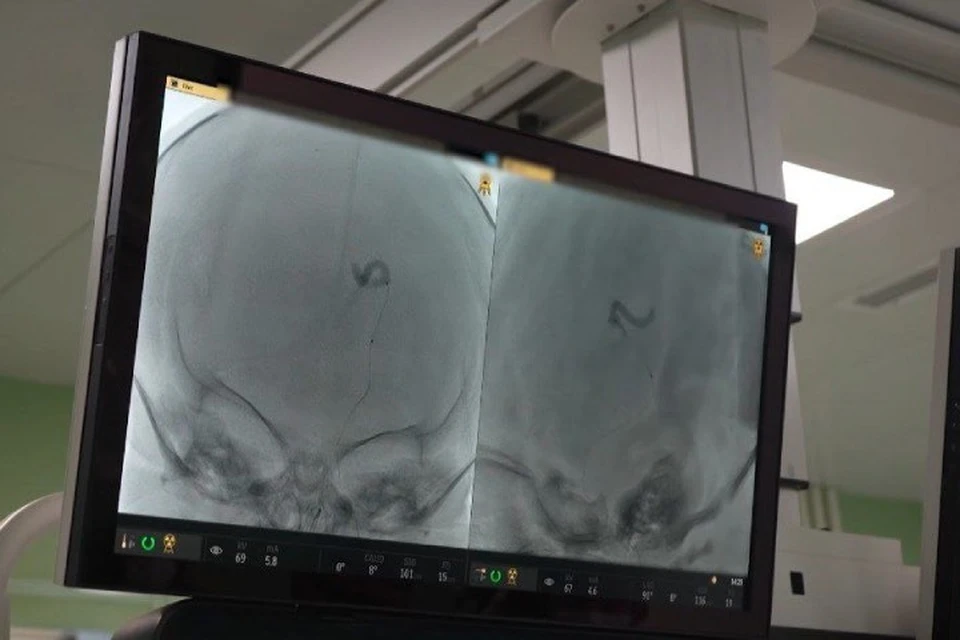

Впервые в Иркутской областной детской клинической больнице врачам удалось спасти жизнь новорожденному с редчайшей патологией мозга – артериовенозной мальформацией вены Галена. Состояние малыша было критическим: его сердце работало на пределе из-за огромного давления, пациент мог умереть в первые же дни жизни.

- Специалистам удалось заблокировать почти половину кровеносных сосудов. Работа велась с младенцем, который родился всего пять дней назад с весом менее трех килограммов, - уточняется в сообщении.

Благодаря вмешательству давление на сердце снизилось, ребенок смог дышать самостоятельно. Это первый этап лечения, дальше предстоит реабилитация. Раньше такие операции проводили только в Москве и Новосибирске, а теперь высокотехнологичная помощь доступна и в Иркутске, что сокращает риски, связанные с перевозом критически больных новорожденных.